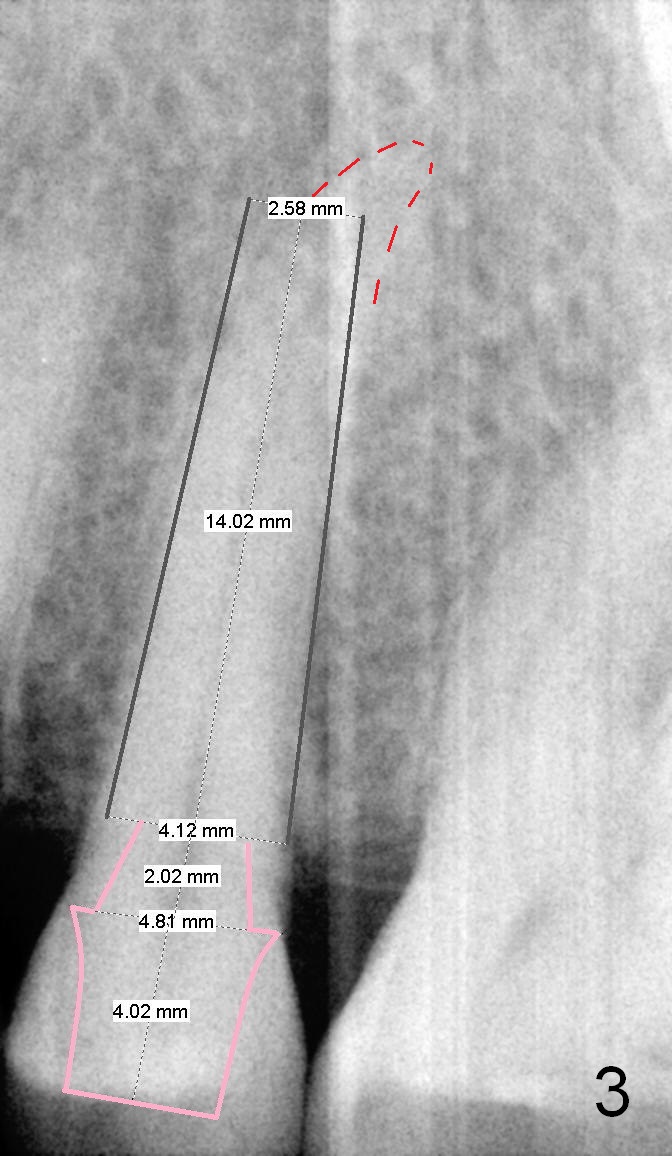

A 67-year-old lady (CC) has an implant at the site of #3, which replaces the fractured tooth (Fig.1). Recently the tooth #13 also fractures subgingivally (Fig.2). The tooth has a long and curved root. All of these suggest that the patient is a bruxer. The bone density is high. After extraction and placement of Clindamycin gauze in the socket, a 2 mm pilot drill is used to start osteotomy ~17 mm from the gingival margin, followed by 2.5 mm reamer ~ 17 mm, and 3 for 14 mm. If the socket looks small (mesiodistally), the goal is to place 4.1x14 (Fig.3) or 13 mm (Fig.4) implant. Otherwise use 4.5x17 mm Tatum tapered tap at 14 mm and plan to place a 4.5x13 or 14 mm implant. If it is difficult to insert an implant, use one size smaller drill from its original cassette or use 5x17 mm tap at 11 mm (to open up the entrance of the osteotomy). If the implant or tap is being deviated buccally while it is placed, use a Lindermann bur from Bicon Restorative plastic box to remove the bone from the palatal wall. When the side-cutting drill is cleaned, keep it in the Bicon Surgical Cassette. If the bone density turns out to be low, osteotomy depth will be 20 mm instead (Fig.5). When the flutes of 2.5 and 3 mm reamers collects bone particles, the bone density is high.